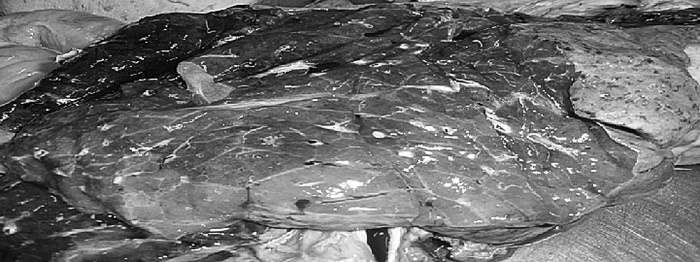

Рис. 1. Результаты аутопсии больного 68 лет

Мускатная печень

Полнокровные легкие